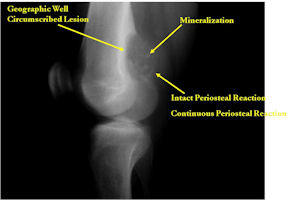

Plain X-rays:

- Geographic, circumscribed lesion usually around 5cm in size.

- There may be expansion of bone, cortical thinning and cortical breakthrough. A soft tissue mass may accompany this lesion but the soft tissue component is usually contained by the periosteum.

- The periosteum remains intact around the soft tissue component. Might need a CT scan to detect the subtle calcification (Egg Shell Rim of Calcification) associated with an intact periosteal reaction

- The lesion may be entirely radiolucent but usually shows some degree of mineralization. Mineralization may appear stippled like cartilage but do not see chondroid pathologically. Mineralization is sometimes better detected on a CT scan rather than an x-ray.

- Usually less surrounding sclerosis than an osteoid osteoma.

- Arise from the Diaphysis (75%) more commonly than Metaphyseal (25%)

- 4 cm to 6 cm in size